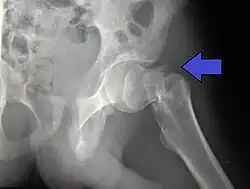

Subcapital fracture in a 92-year-old woman

X-rays of the affected hip usually make the diagnosis obvious; AP (anteroposterior) and lateral views should be obtained.